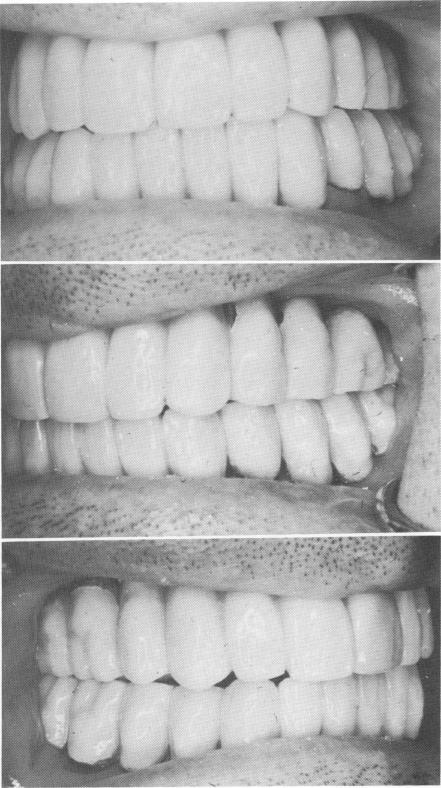

Fig. 11-163. The finished acrylic-over-gold prostheses.

Fig. 11-164. The prostheses were articulated.

1 Dental case articulated on Hanau articulator

2 Finished acrylic over gold maxillary & mandibular prostheses

3 Maxillary and mandibular prostheses articulated